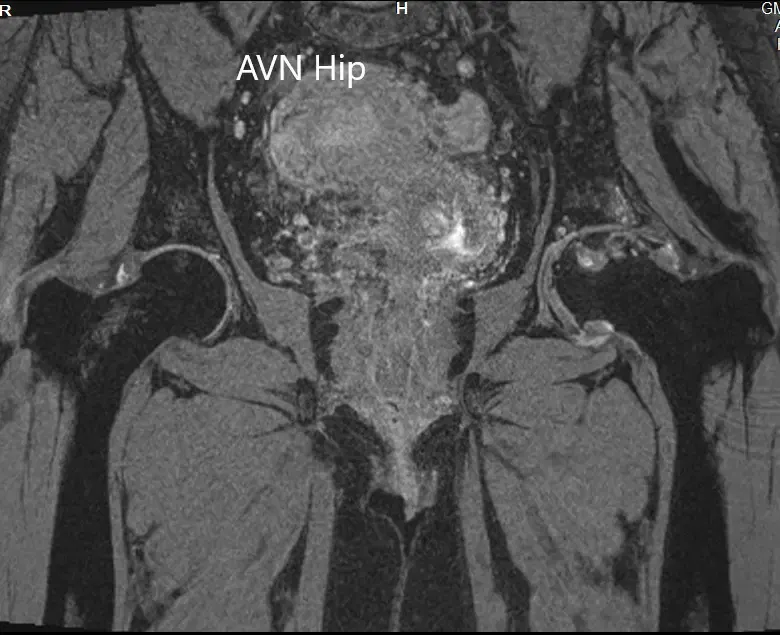

Se realizó una resonancia magnética que mostró una intensidad de señal alterada tanto en T1WI como en T2WI. Hubo un colapso sutil de la cabeza femoral izquierda. Se observó una línea sérpinosa e hiperintensa en T2WI que delimitaba una zona de osteonecrosis en la cabeza femoral izquierda. Esta zona afectaba al compartimento lateral y medial y cubría más del 50% de la superficie de la cabeza.

Se visualizaron cambios osteoartríticos secundarios en forma de reducción del espacio articular anterosuperior y formación de osteófitos. Se observó una pequeña cantidad de líquido en la cavidad articular.

Imagen de resonancia magnética T2WI mostrando la sección coronal.